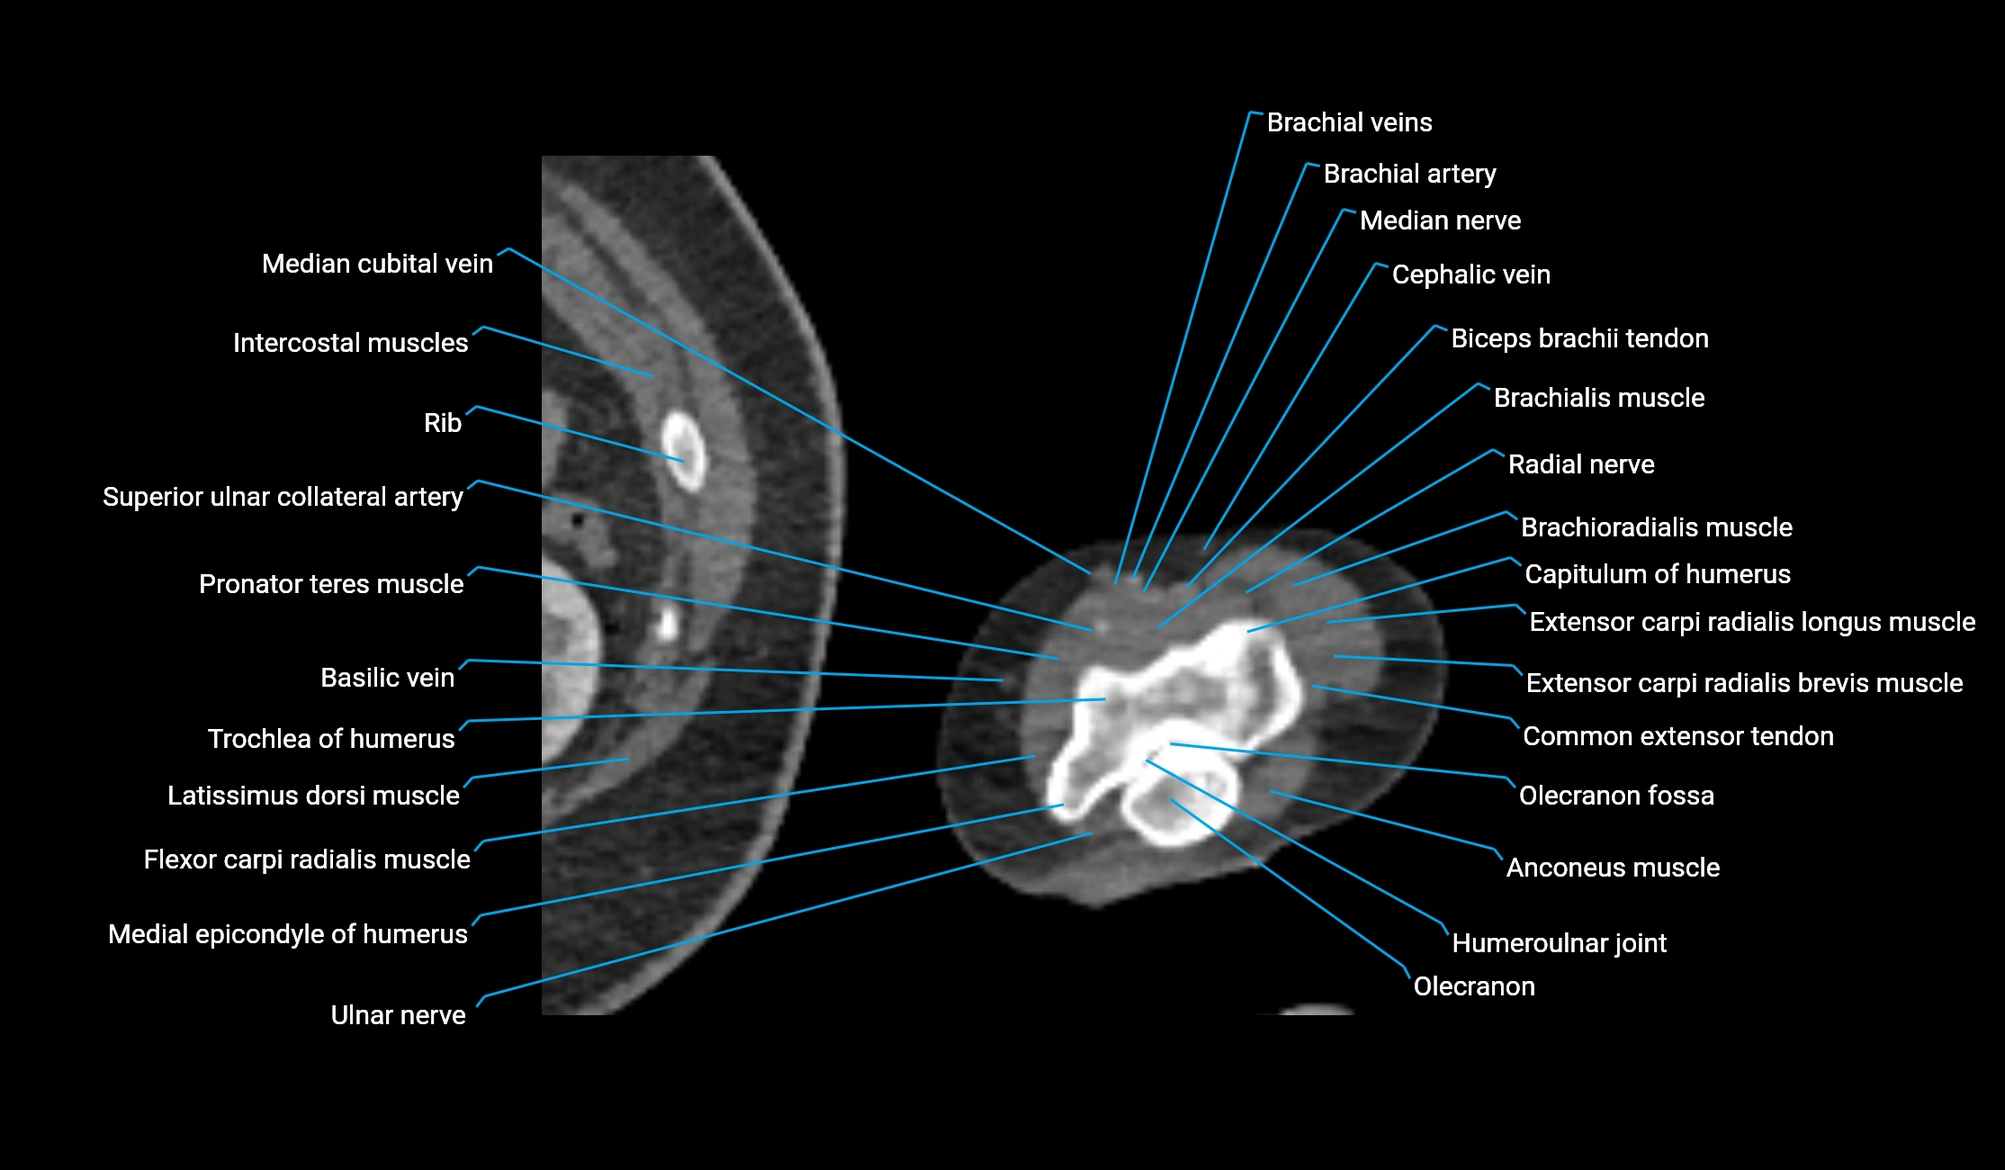

- Basilic vein

- Brachial artery

- Brachialis muscle

- Brachioradialis muscle

- Capitulum of humerus

- Cephalic vein

- Common extensor tendon

- Extensor carpi ulnaris muscle

- Flexor carpi radialis muscle

- Humeroulnar joint

- Lateral head of triceps brachii muscle

- Latissimus dorsi tendon

- Medial epicondyle of humerus

- Median cubital vein

- Median nerve

- Olecranon

- Olecranon fossa

- Radial nerve

- Superior ulnar collateral artery

- Trochlea of humerus

- Ulnar nerve